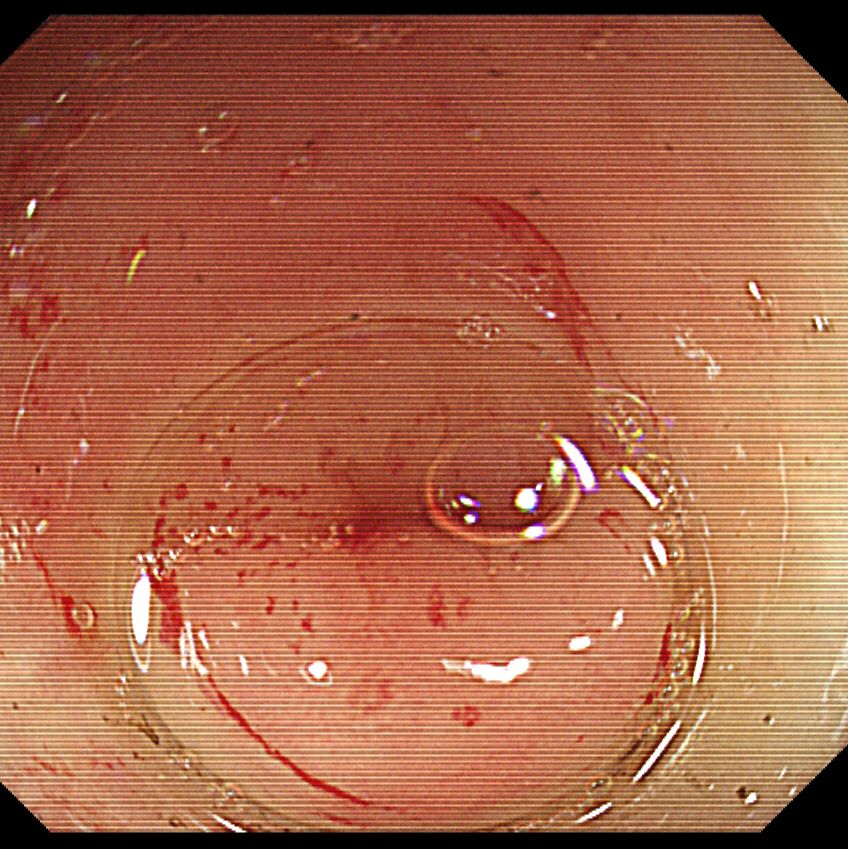

5、术后阑尾腔

图片